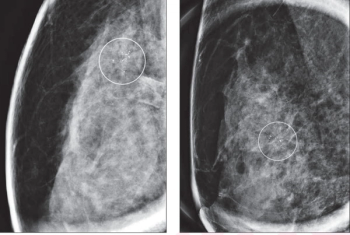

A proposed alternative to a previously validated deep learning neural network for assessing short-term breast cancer risk, the emerging AsymMirai deep learning mammography-based model showed comparable breast cancer risk prediction with an emphasis on bilateral dissimilarity, according to new research.